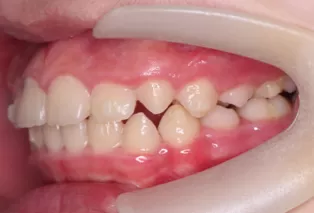

Intraoral photos